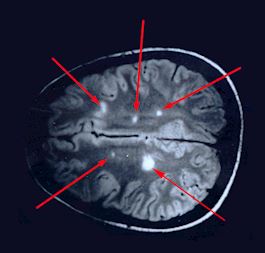

MRI Results

Cerebral Hemisphere

Arrows point to plaques or areas of demyelination